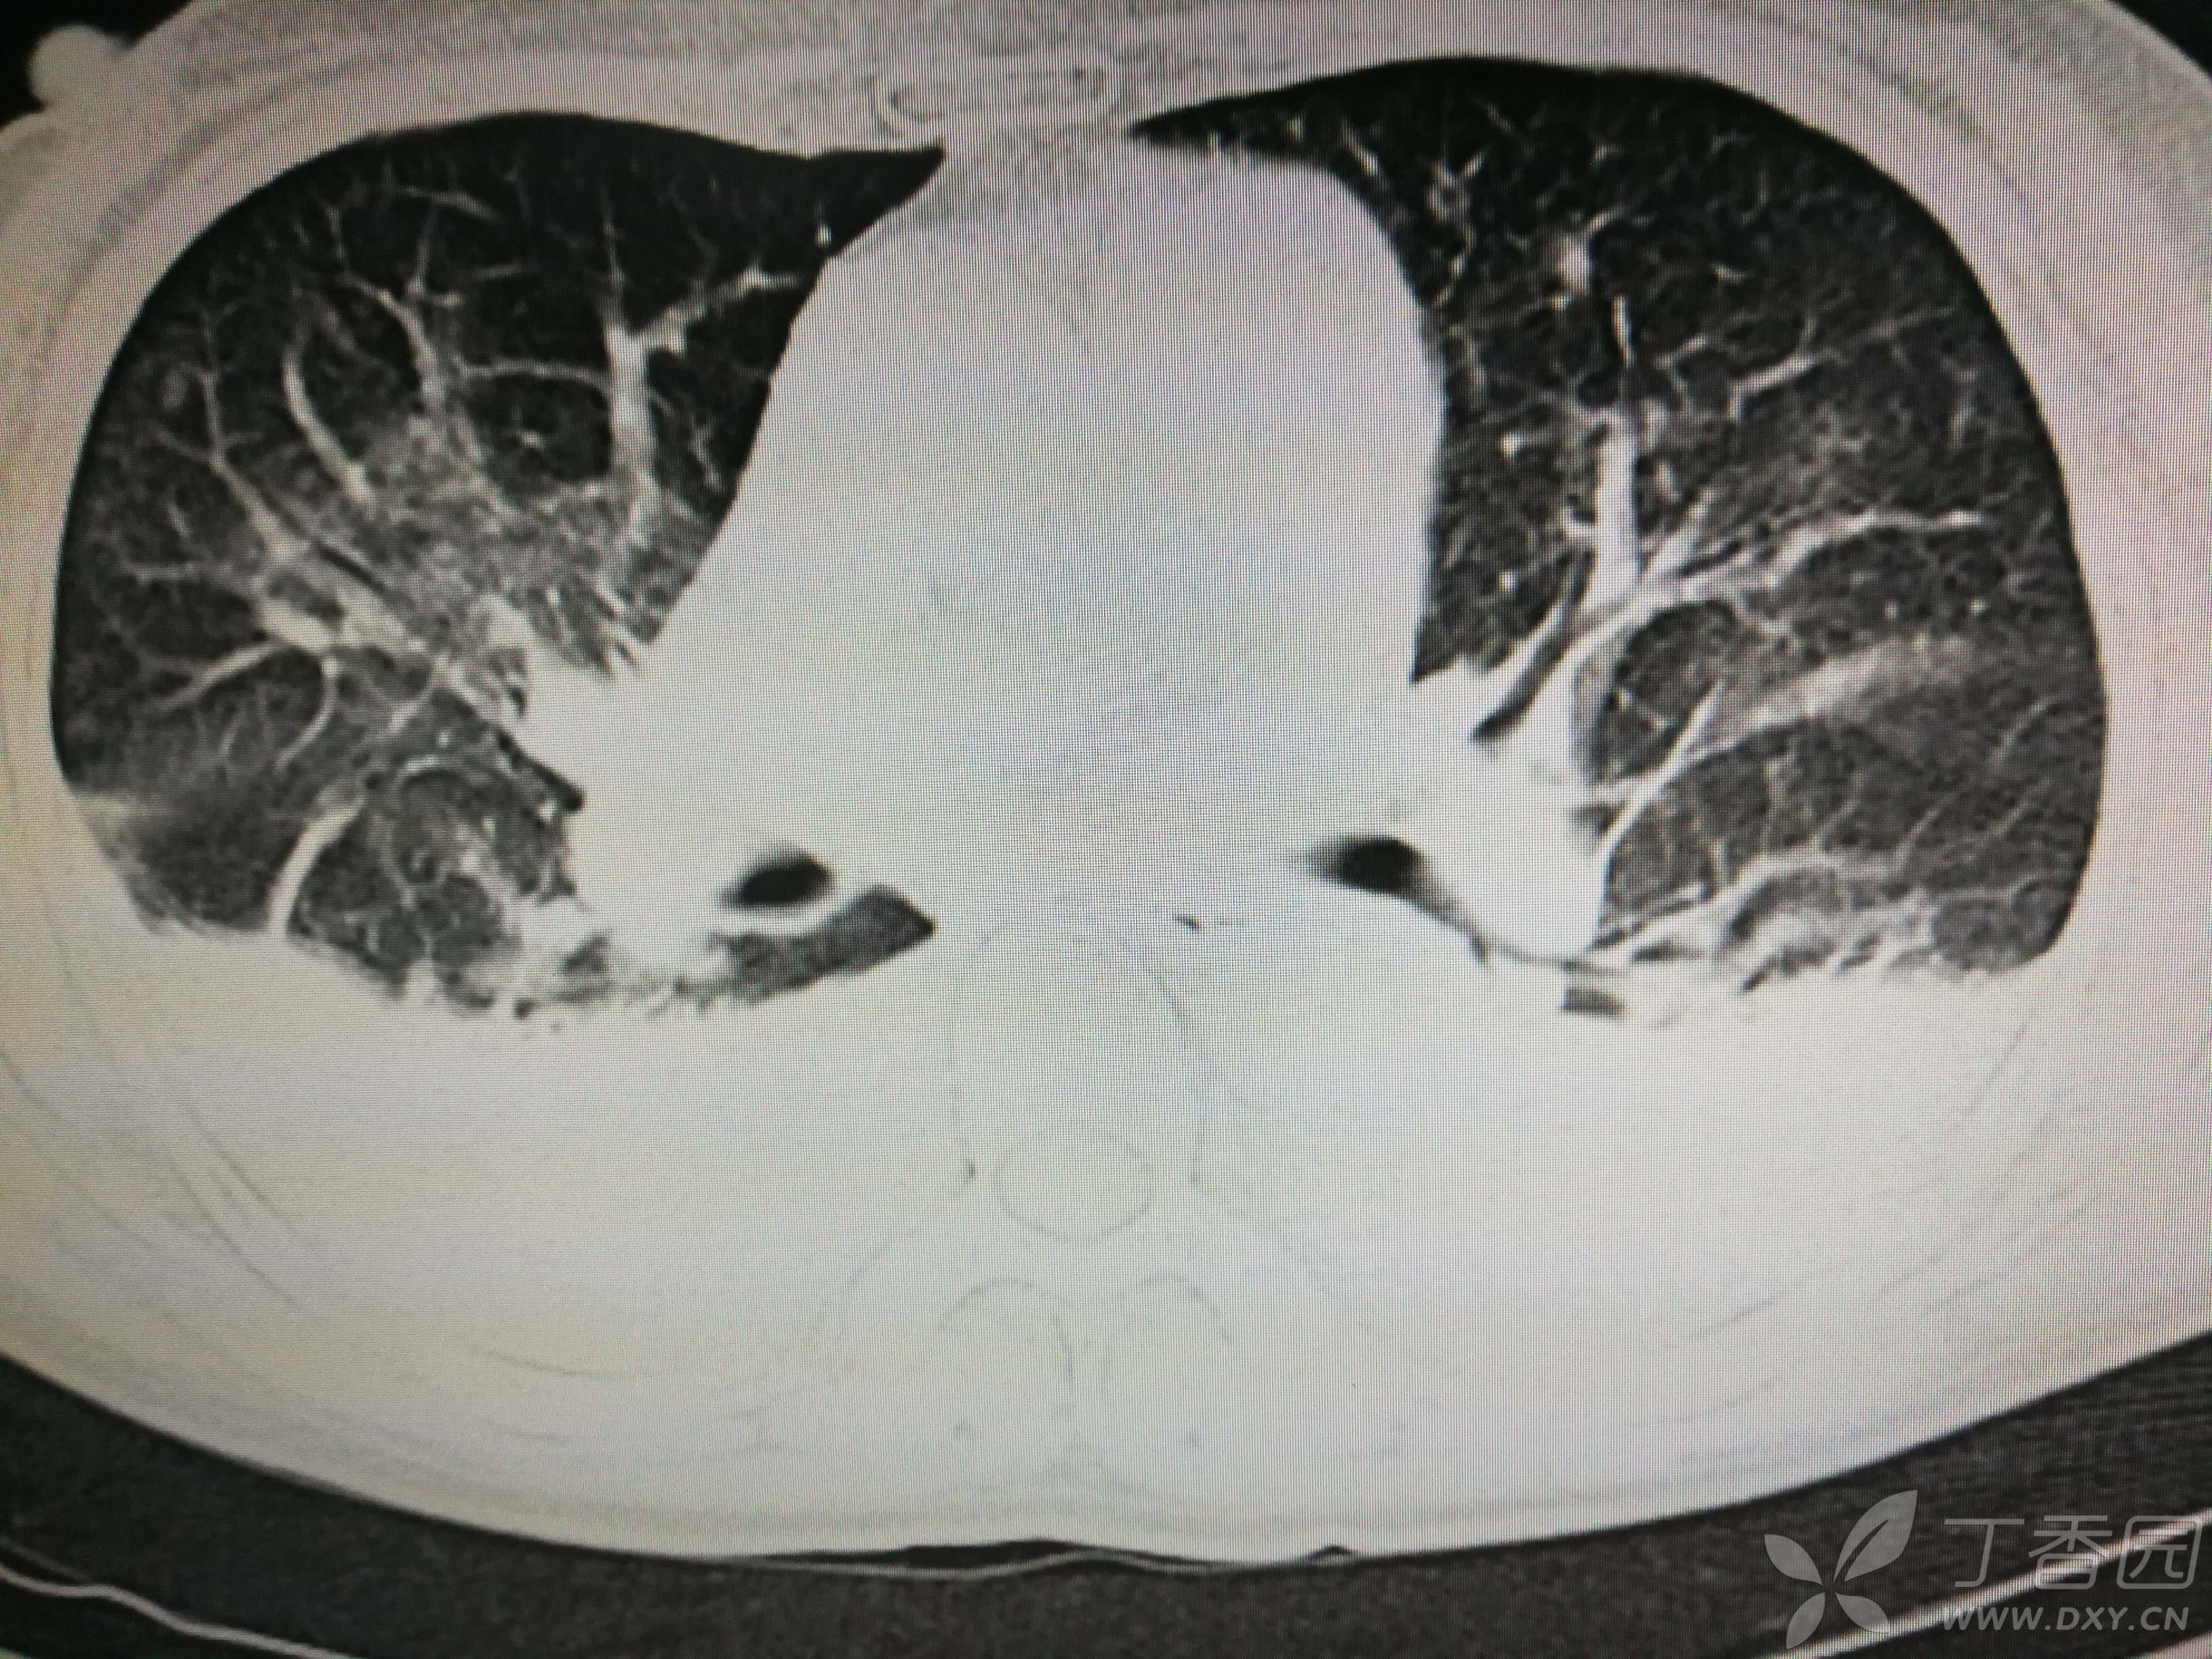

给予低分子肝素钙针抗凝、七叶皂苷钠针消肿及骨牵引固定等等治疗。入院后第四天行“左侧股骨下段骨折切开复位内固定术”(术前查双下肢彩超:双下肢深静脉血流通畅),手术顺利,术后予预防感染、预防血栓形成等治疗。术后患者无明显发热,生命体征平稳。术后第四天复查血常规:白细胞13.4×109/L,血红蛋白84g/L,血小板在正常范围。生化:白蛋白35.7g/L,余无明显异常。当天,患者开始出现轻度胸闷气急,可耐受。术后第五天患者胸闷气急加重,无胸痛,无背痛,无咯血,无意识障碍,无头晕头痛,无恶心呕吐等,急查凝血功能:纤维蛋白原降解产物12mg/L,D二聚体4000ug/L,余无明显异常。查动脉血气分析:pH7.52,氧分压62mmHg,二氧化碳分压30mmHg,碱剩余1.8mmol/L,乳酸1.0mm/L,血红蛋白86g/L。查胸部CT见下(先视频后图片):